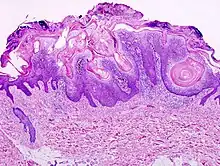

Visual diagnosis is made by the "stuck on" appearance, horny pearls or cysts embedded in the structure. Darkly pigmented lesions can be challenging to distinguish from nodular melanomas.[10] Furthermore, thin seborrheic keratoses on facial skin can be very difficult to differentiate from lentigo maligna even with dermatoscopy. Clinically, epidermal nevi are similar to seborrheic keratoses in appearance. Epidermal nevi are usually present at or near birth. Condylomas and warts can clinically resemble seborrheic keratoses, and dermatoscopy can be helpful to differentiate them. On the penis and genital skin, condylomas and seborrheic keratoses can be difficult to differentiate, even on biopsy.

A study examining over 4,000 biopsied skin lesions identified clinically as seborrheic keratoses showed 3.1% were malignancies. Two-thirds of those were squamous cell carcinoma.[11] To date, the gold standard in the diagnosis of seborrheic keratosis is represented by the histolopathologic analysis of a skin biopsy.[12]